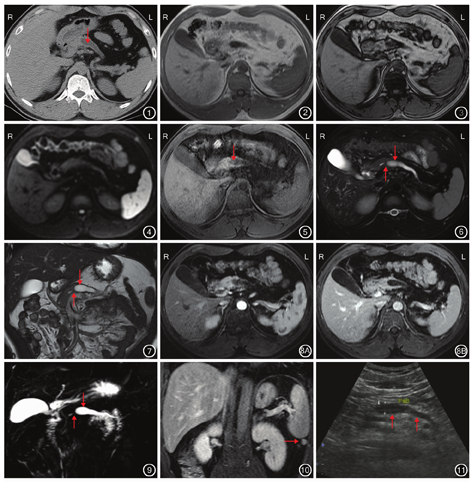

CT检查:胰腺长度未见异常,胰体、尾部实质萎缩,胰头部体积稍增大,胰腺实质密度均匀,胰体、尾部主胰管扩张。见图1。

MRI检查:(1)胰头部:T1WI、T2WI示胰头部体积稍增大,实质信号均匀,同、反相位无信号衰减(图2,图3),DWI无弥散受限(图4),增强扫描均匀明显强化。(2)胰体、尾部:T1WI、T2WI示胰体、尾部变细,实质萎缩、变薄(图5,图6),DWI无弥散受限,增强扫描未见异常强化灶。(3)胰管与胆管:①胰体、尾部主胰管明显扩张(图5),内壁光整,胰体部较宽,颈部主胰管变窄(图6,图7),胰头部主胰管无扩张,增强扫描见扩张的胰管内无异常强化灶(图8);分支胰管均未见扩张。②MRCP检查示肝内、外胆管、胆囊未见扩张(图9),腔内未见异常信号。(4)胰腺边缘:光滑、规则,胰周脂肪间隙清晰。(5)其他表现:脾脏下缘见一圆形软组织信号影,平扫及增强扫描信号强度均与脾脏一致(图10)。

(1)主胰管:最大宽径为12.6 mm,扩张长度为91.6 mm。(2)胰腺实质:背胰宽度为19.6 mm,腹胰宽度为26.7 mm。(3)其他径线:腹胰-中线为54.6 mm,背胰-中线为77.3 mm,背胰-脾门为18.5 mm。

2014年11月,患者实验室检查示血常规、生化检查、血清肿瘤标志物(AFP、CEA、CA19-9)、尿常规均正常;超声检查:胰头部体积稍增大,内部回声分布均匀,胰体、尾部缩小,主胰管扩张(图11),最大宽径约为12.3 mm。